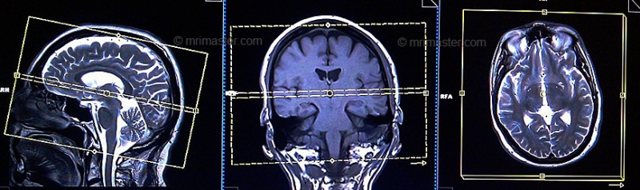

Трехмерная (3D) времяпролетная ангиография time-of-flight (TOF) МRА является наиболее распространенным методом, используемым для оценки системы артериального кровоснабжения головного мозга.

МРА 3D TOF обеспечивает более высокий сигнал-шум (signal-to-noise) и короткое время обработки изображений. MРA головного мозга проста в выполнении и не требует контрастного усиления.

Рекомендуемые протоколы, параметры и планирование

Локалайзер

Первично при планировании последовательности должны быть выполнены снимки в 3 плоскостях. Выдержка снимков менее 25 сек, с получением Т1-взешенных изображений низкого разрешения.

Серия Т2 турбо спин-эхо, аксиальный срез

Планирование аксиальных срезов на сагиттальной плоскости; угловое расположение блока должно быть параллельно колену и валику мозолистого тела.

Эти срезы должны полностью покрывать головной мозг от темени до уровня большого затылочного отверстия. Проверьте расположение блока на 2-х других плоскостях.

Соответствующий угол должен быть получен в коронарной плоскости при наклонном положении головы (перпендикулярно линии, соединяющей третий желудочек и ствол головного мозга).

Времяпролетная ангиография 3D (time-of-flight, TOF)

Планирование аксиальных 3D – блоков на сагиттальной плоскости; угловое расположение блока должно быть параллельно колену и валику мозолистого тела. Эти срезы должны полностью покрывать Виллизиев Круг от уровня мозолистого тела до уровня большого затылочного отверстия.

Проверьте расположение блока на 2-х других плоскостях. Соответствующий угол должен быть получен в коронарной плоскости при наклонном положении головы (перпендикулярно линии, соединяющей третий желудочек и ствол головного мозга).